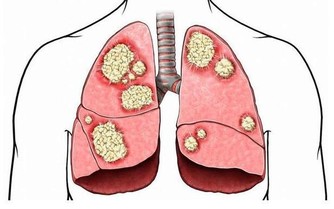

4、早上起床後如果有頭昏腦漲,胸悶氣短等情況,說明脾胃功能較為虛弱。從中醫角度來看,脾臟和肺的功能會相互影響,脾臟虛弱到一定程度後,容易影響肺部正常功能,表現為氣短,氣促或者是肺氣虛。